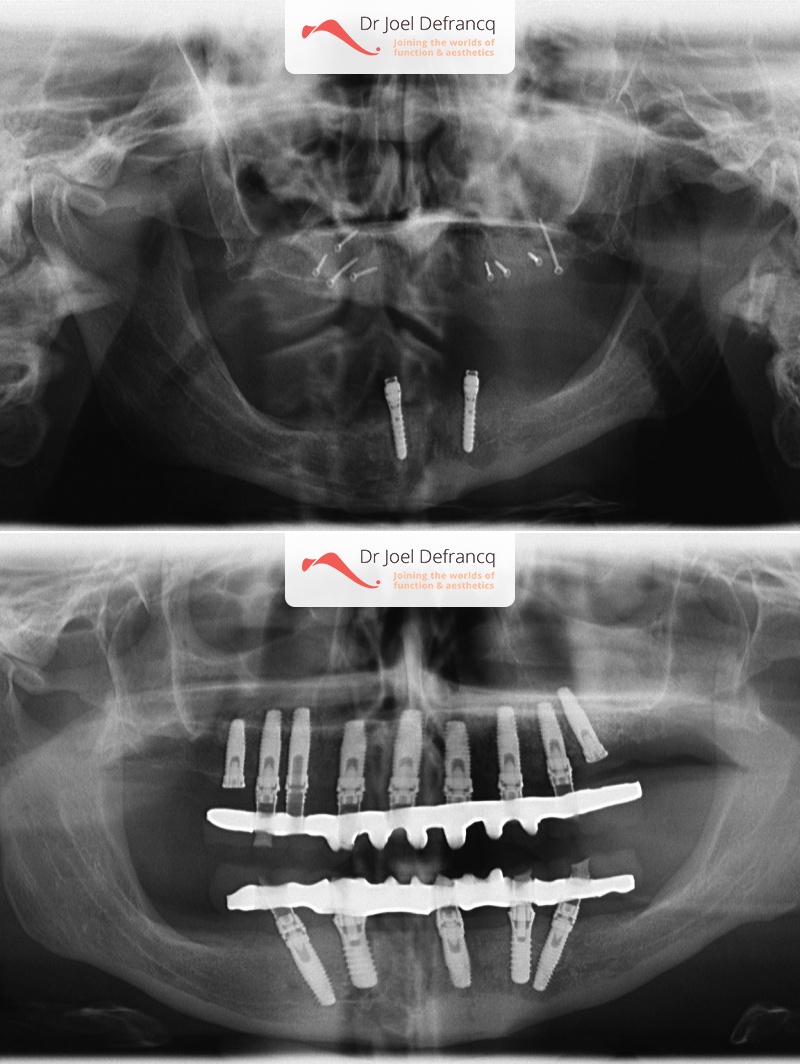

Behandeling tandheelkundige implantaten

- Vaste tanden op implantaten (bovenkaak)

- Vaste tanden op implantaten (onderkaak)

- Implantaten met beenopbouw